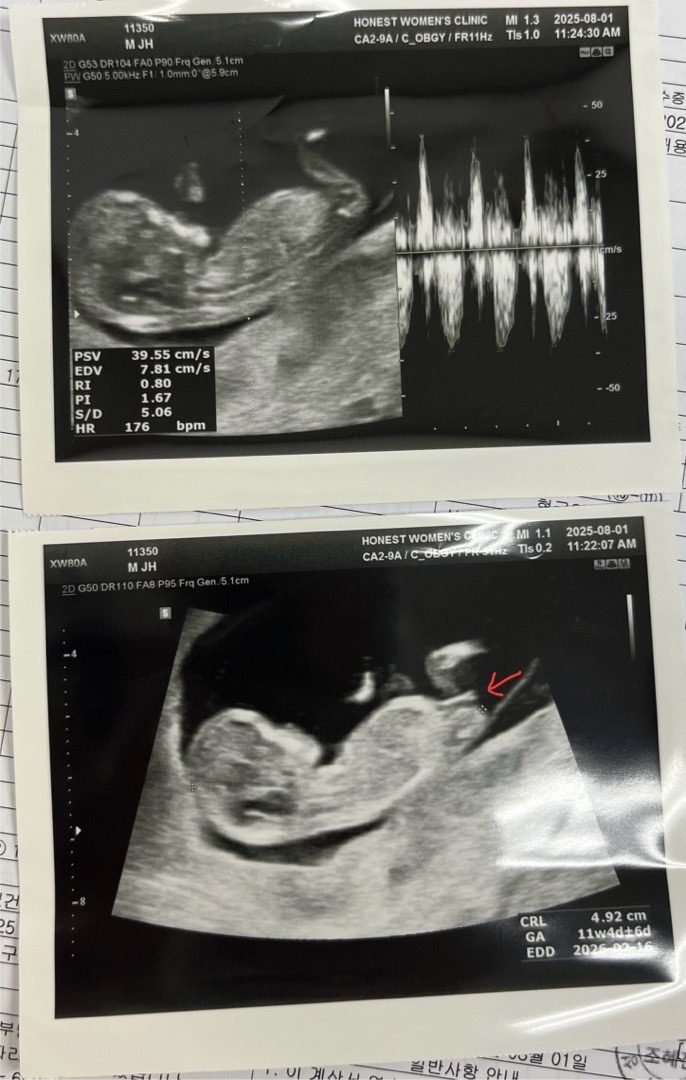

피고임 있어서 병원 갔는데 성별 궁금쓰🥲

11주차 들어서면서 마음 좀 놓아야겠다 했는데 오늘 갑자기 갈색혈이 나와서 첨으로 서브병원 가봤어요 그랬더니 왠걸 아기크기만한 피고임이 있다해서 주사 맞고 질정 처방 나왔네요 ㅜㅜ 초음파 사진 받고 이르겠지만 자꾸 성별이 궁금한데, 아래 사진 화살표 부분이 조금 길어서? 혹시 아들인가요...?

끝에가 갈라져 있으면 딸이라던데요? ㅎㅎ 딸 아닐까요?

엇 그런가요?! 끝이 분명히 갈라져있어요😳